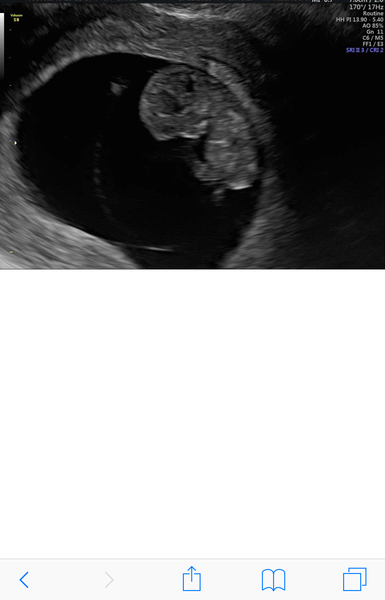

AIDE2424 · 27/12/2018 20:30

Here’s what baby pip looked like at 7+3 can’t bekieve how much they change in such a short amount of time!x